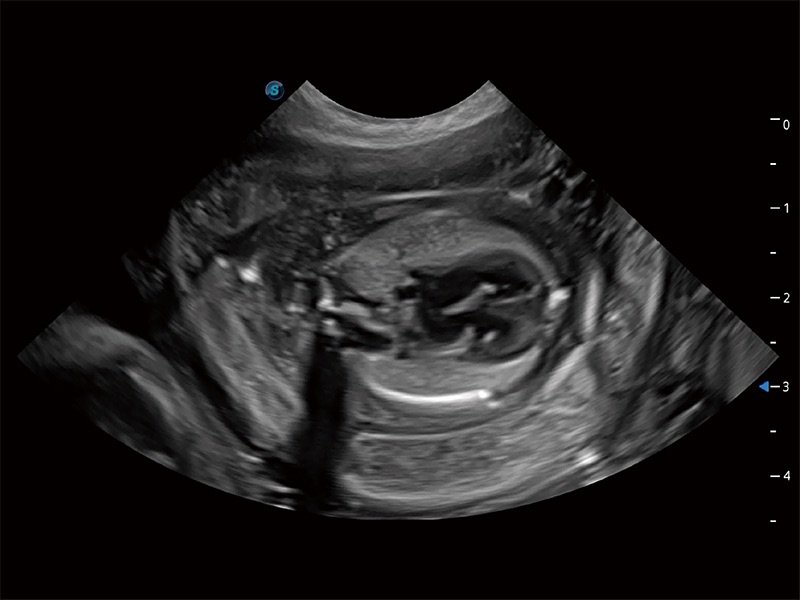

非线性融合造影成像充分利用谐波和基波信号,为难以观察的血流进行增强显像。可用于线阵、凸阵、微凸阵、相控阵探头。